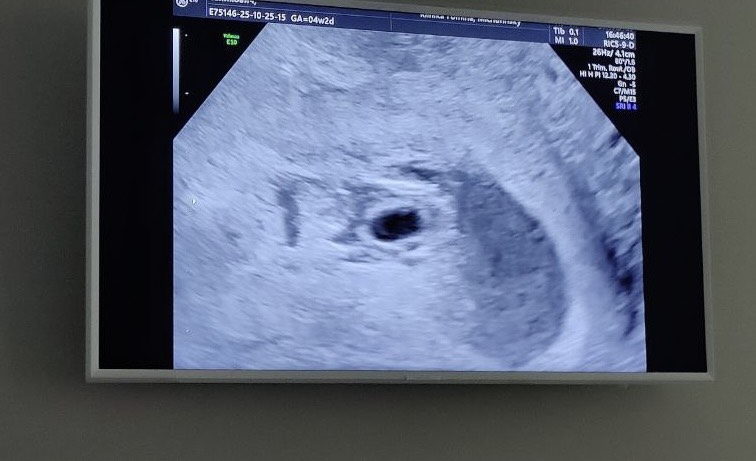

4 недели 3 дня

Сегодня было наше первое УЗИ.

Подтвердили маточную беременность, по всем параметрам все отлично 🤞🏻

Через 2 недельки сказали приходить на следующее узи, смотреть эмбрион и слушать сердечко.